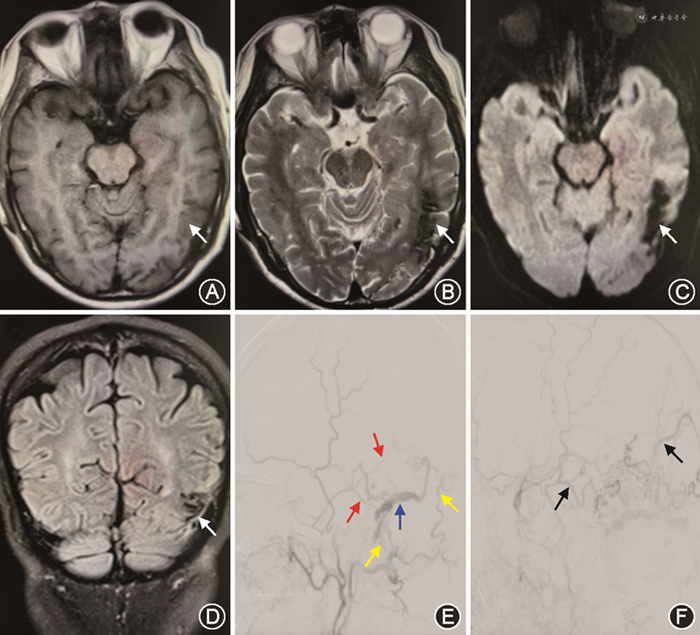

DSA是明确DAVF诊断和分型的“金标准”,可以清楚地显示供血动脉的来源、瘘口的位置、受累的静脉窦有无栓塞及观察静脉回流的方向(图2)。选择性DAVF血管造影应完善6根血管检查:双侧颈内动脉、颈外动脉和椎动脉,如病变位于枕大区者,则加做上颈段血管造影,如双侧甲状颈干造影。DAVF区别于BAVM的特征有如下几点:(1)供血动脉来自颈内动脉、颈外动脉、椎动脉的脑膜支或硬脑膜动脉;(2)无畸形血管团;(3)瘘口位于硬脑膜上而不是脑内。Lang等[23]使用基于人工智能的三维血管造影成像后处理技术,重建脑动脉瘤(10例)、BAVM(10例)和DAVF(10例)的数据影像,发现对血管结构的评估与3D-DSA相当,并大大减少患者的辐射剂量。四维数字减影血管造影(4D-DSA)作为一项新技术,已经引起了人们的关注。Ishikawa等[24]对10例接受了3D-DSA和4D-DSA的检查的DAVF患者进行比较,发现通过3D-DSA获得的MPR图像对供血动脉和瘘口的可见度明显优于通过4D-DSA获得的图像(P<0.05),但诊断准确率差异无统计学意义。

随着介入栓塞材料的发展,血管内介入治疗已成为DAVF的首选治疗方法,可以选择经动脉栓塞或静脉栓塞的途径(图3)。Chen等[28]回顾了415例未破裂的高级别(Borden Ⅱ型或Ⅲ型)DAVF患者,并根据最初的处理方法将其分为4组[保守治疗、栓塞、手术和立体定向放射手术(SRS)],结果表明介入栓塞治疗后完全闭塞率更高,同时减少了DAVF出血及死亡的风险。这些发现支持将介入栓塞作为未破裂的Borden Ⅱ型和Ⅲ型DAVF的一线治疗选择。